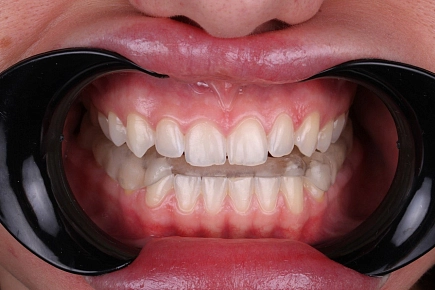

Исправление прикуса брекетами с каждым годом набирает популярность